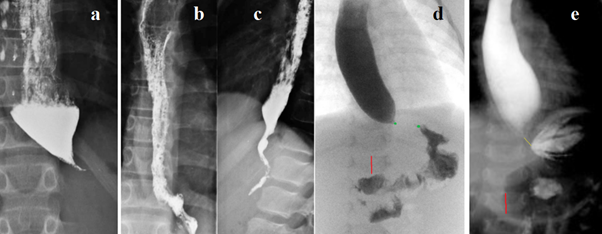

Figure 5

(a) The 11-year-old girl had suffered from obstructive bronchitis for several years. She complained of problems when swallowing solid food and drank large amounts of water during her meals to support swallowing the ingested food. Insertion of the endoscope into the stomach was easily achieved. Based on the clinical symptoms and radiological picture, the authors diagnosed EA and performed a laparoscopic Heller myotomy combined with Dor fundoplication. They created the myotomy of the cardia on the lesser curvature of the stomach and distal esophagus to 5 cm above the hiatus of the diaphragm. (b,c) Contrast study of esophagus with barium sulphate obtained 2 months after surgery.47 Analysis. Sharply dilated esophagus with a cone-shaped narrowing to 3 mm for 2.5 cm at the distal end of the esophagus, which corresponds to the normal length of the LES at a given age, the absence of gas in the stomach and the free passage of the endoscope into the stomach completely correspond to the concept of EA. This is the only case (3% of 29) where the radiographic conclusion about EA is not in doubt. But to finally resolve the question of whether EA is a result of GERD, it was necessary during operations to perform a histological examination of the LES tissue.

(d) The authors report a 9-month-old female with achalasia and alacrima (also known as AAA syndrome or Allgrove or Triple A syndrome). She had gastroesophageal reflux. Despite taking histamine‐2 receptor blockers, and proton pump inhibitors, her symptoms persisted. The clinical and radiographic findings were concerning for achalasia. Endoscopy with biopsy showing mild dilation of the esophagus and a subjectively hypertensive LES. Esophageal manometry findings confirmed a diagnosis of type II achalasia. Due to the patient's feeding difficulty and aspiration risk, a gastrostomy tube was placed to ensure proper nutrition while surgical options were discussed.48 Analysis. The case report states that she had gastroesophageal reflux. “Subjectively hypertensive LES during endoscopy means difficulty in passing the endoscope through the EGJ. These data do not allow us to exclude GERD. At the same time, the length of the LES corresponds to the age norm. Evacuation from the esophagus is sharply slowed down and there is no gas in the stomach. These data, in combination with alacrima, do not allow us to exclude EA.

(е) Ever since birth, in 21-month-old female the patient did not produce tears. A vomiting started at 9 months of age. She received prokinetics, and PPIs with no improvement. A contrast esophagram series showed a bird’s beak appearance. High-resolution esophageal manometry identified type I esophageal achalasia. Alacrima was also diagnosed. The patient underwent laparoscopic Heller cardiomyotomy and partial anterior Dor fundoplication.49 Analysis. The true height of L-1 (red line) is 1.3 cm. Therefore, the length of the contracted LES (yellow line) is 0.6 cm, which is significantly less than the age norm of 1.2–1.5 (1.40 ± 0.02 cm). What the authors call the bird’s beak appearance is the open supradiaphragmatic part of the LES. A sharp shortening of the LES indicates an opening of the abdominal part of the LES, which is characteristic of GERD. A large amount of gas in the stomach and intestines indicates sufficient patency of the EGJ. A double contour of the lower part of the esophagus may be a symptom of esophagitis, which at the level of the LES worsens its patency. Conclusion. Elevated levels of GDP-mannose in AAA syndrome contribute to neuronal degradation and loss of motor skills. However, we only know for sure about an alacrima. The presence of EA is questionable.